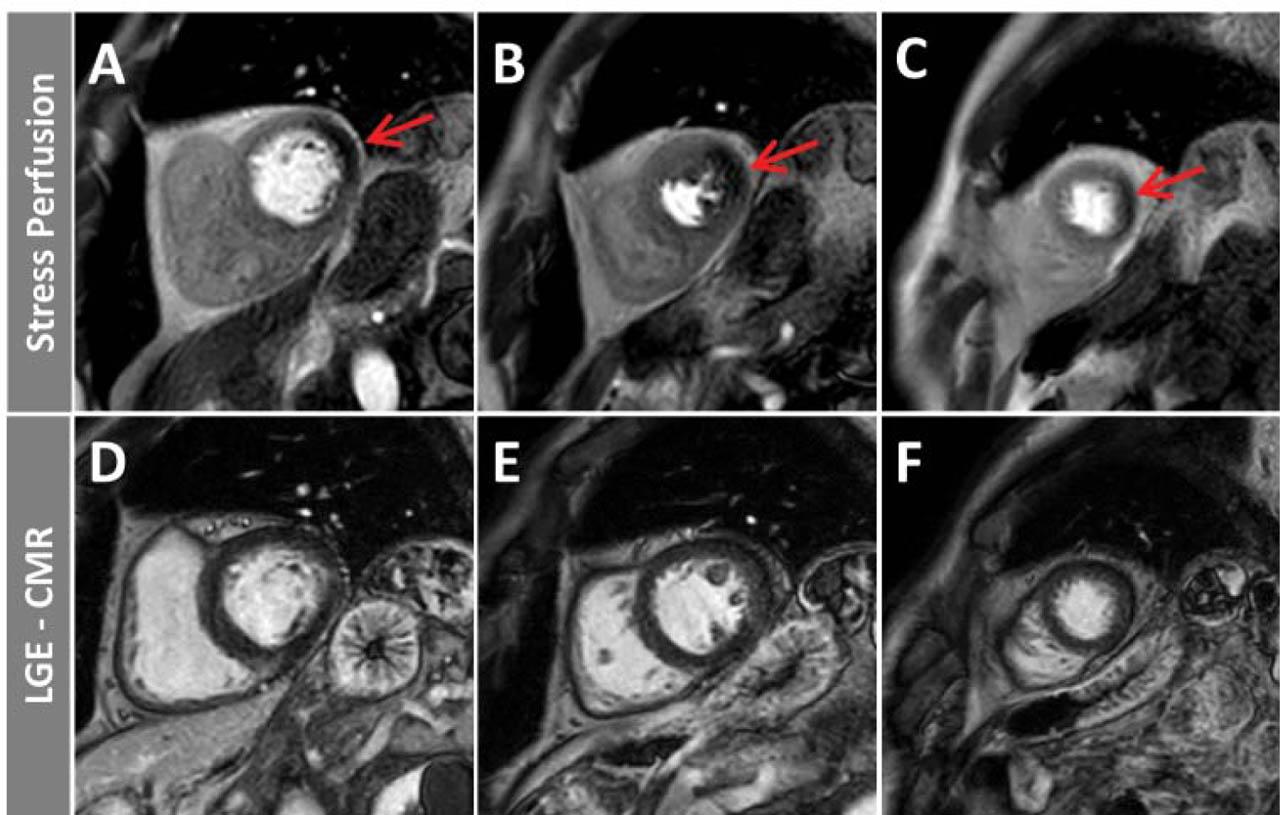

Figure 5

Edema sensitive T2-STIR in apical short-axis (A) and LGE images in apical short-axis (B) and two-chamber (C) view in a patient with myocardial infarction and no obstructive coronary arteries (MINOCA). A small, acute ischemic myocardial damage in the septal/inferior apical myocardial segments with edema (T2-hyperintesity, red arrow) and LGE (white arrows) can be seen. Within the LGE area, a small dark core of microvascular obstruction is also noticeable.